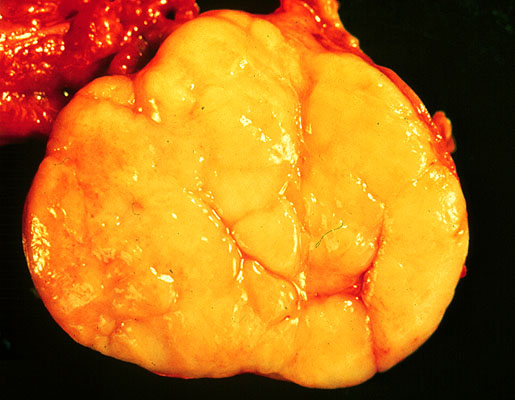

Seminoma, gross, cut surface

The testis contains a yellow lobulated mass that is sharply demarcated from the normal brown testicular tissue. The cut surface of the tumor appears uniformly yellow and shows no areas of necrosis or hemorrhage.